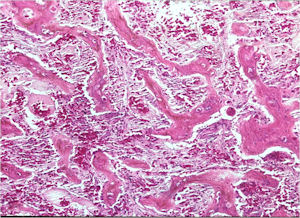

Microscopic Pathology

- Interlacing network of bone trabeculae in a loose fibrovascular stroma

- Prominent vessels

- Osteoblasts are plump, active, scattered mitotic figures

- Osteoblasts line up around periphery of trabeculae (Osteoblastic Rimming)

- Soft tissue component usually surrounded by shell of reactive bone or periosteum (Egg Shell Rim of Calcification)

- No cartilage production (as opposed to osteosarcomas that may contain areas of cartilage)